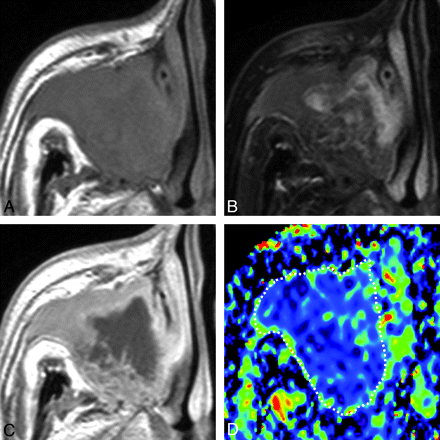

A 65-year-old man with SCC. A, Axial T1-weighted MR image (TR/TE = 500/15 ms) shows tumor with homogeneous signal intensity occupying the right maxillary sinus and extending into the surrounding bony structures. B, Axial FS (SPAIR) T2-weighted MR image (TR/TE = 6385/80 ms) shows tumor with heterogeneous signal intensity. C, Axial contrast-enhanced T1-weighted MR image (TR/TE = 500/15 ms) shows tumor with peripheral enhancement. D, Axial color ADC map shows tumor with a low ADC. Overall ADC = 0.8 × 10−3 mm2/s. Areas with extremely low, low, intermediate, and high ADCs occupy 17%, 78%, 5%, and 0%, respectively, of the tumor.

Overall ADCs of malignant tumors were significantly smaller than those of benign and inflammatory lesions (Figs 2⇓–4 and On-line Tables 1 and 2). There was no significant difference in overall ADCs between benign and inflammatory lesions.

ADC Mapping

ADC mapping demonstrated that disease areas with extremely low and/or low ADCs in malignant tumors were significantly greater than those in benign and inflammatory lesions (Figs 2⇑–4 and On-line Tables 1 and 2).